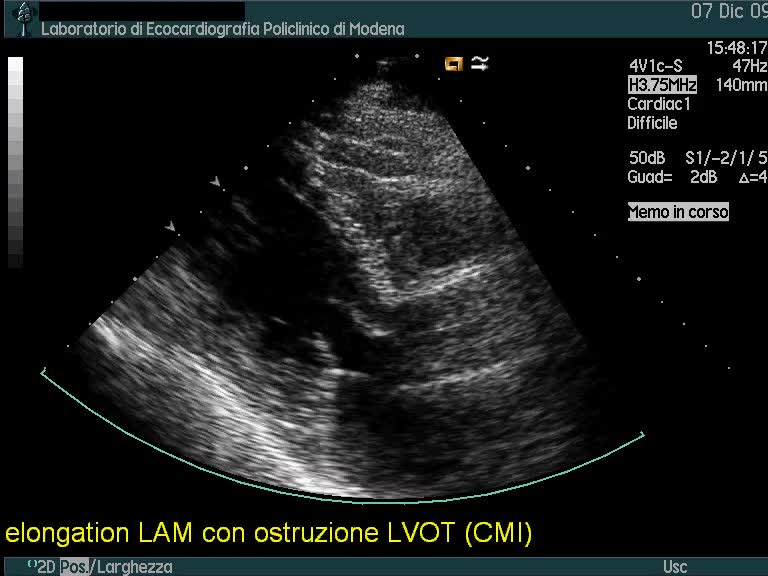

Titolo:

Cardiomiopatia restrittiva

Autore:

Andrea Barbieri